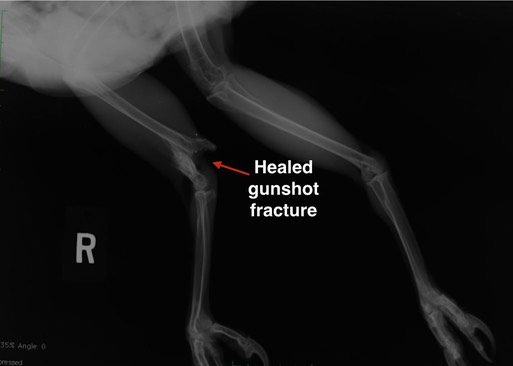

Three More Gunshot Birds

There were 12 admissions this past week. Three were gunshot victims: a Mourning Dove and two Red-tailed Hawks. Red-tailed Hawk 19-075 was especially sad. The hawk had been shot several weeks earlier, fracturing his right leg. Miraculously, the leg had healed. Then, this past week, the hawk suffered fractures in his left wing in a collision, perhaps with a car or power line. The vast majority of BMW patients have been negatively impacted by human activity, either directly or indirectly. For wildlife, in addition to survival of the fittest, it is survival of humans.